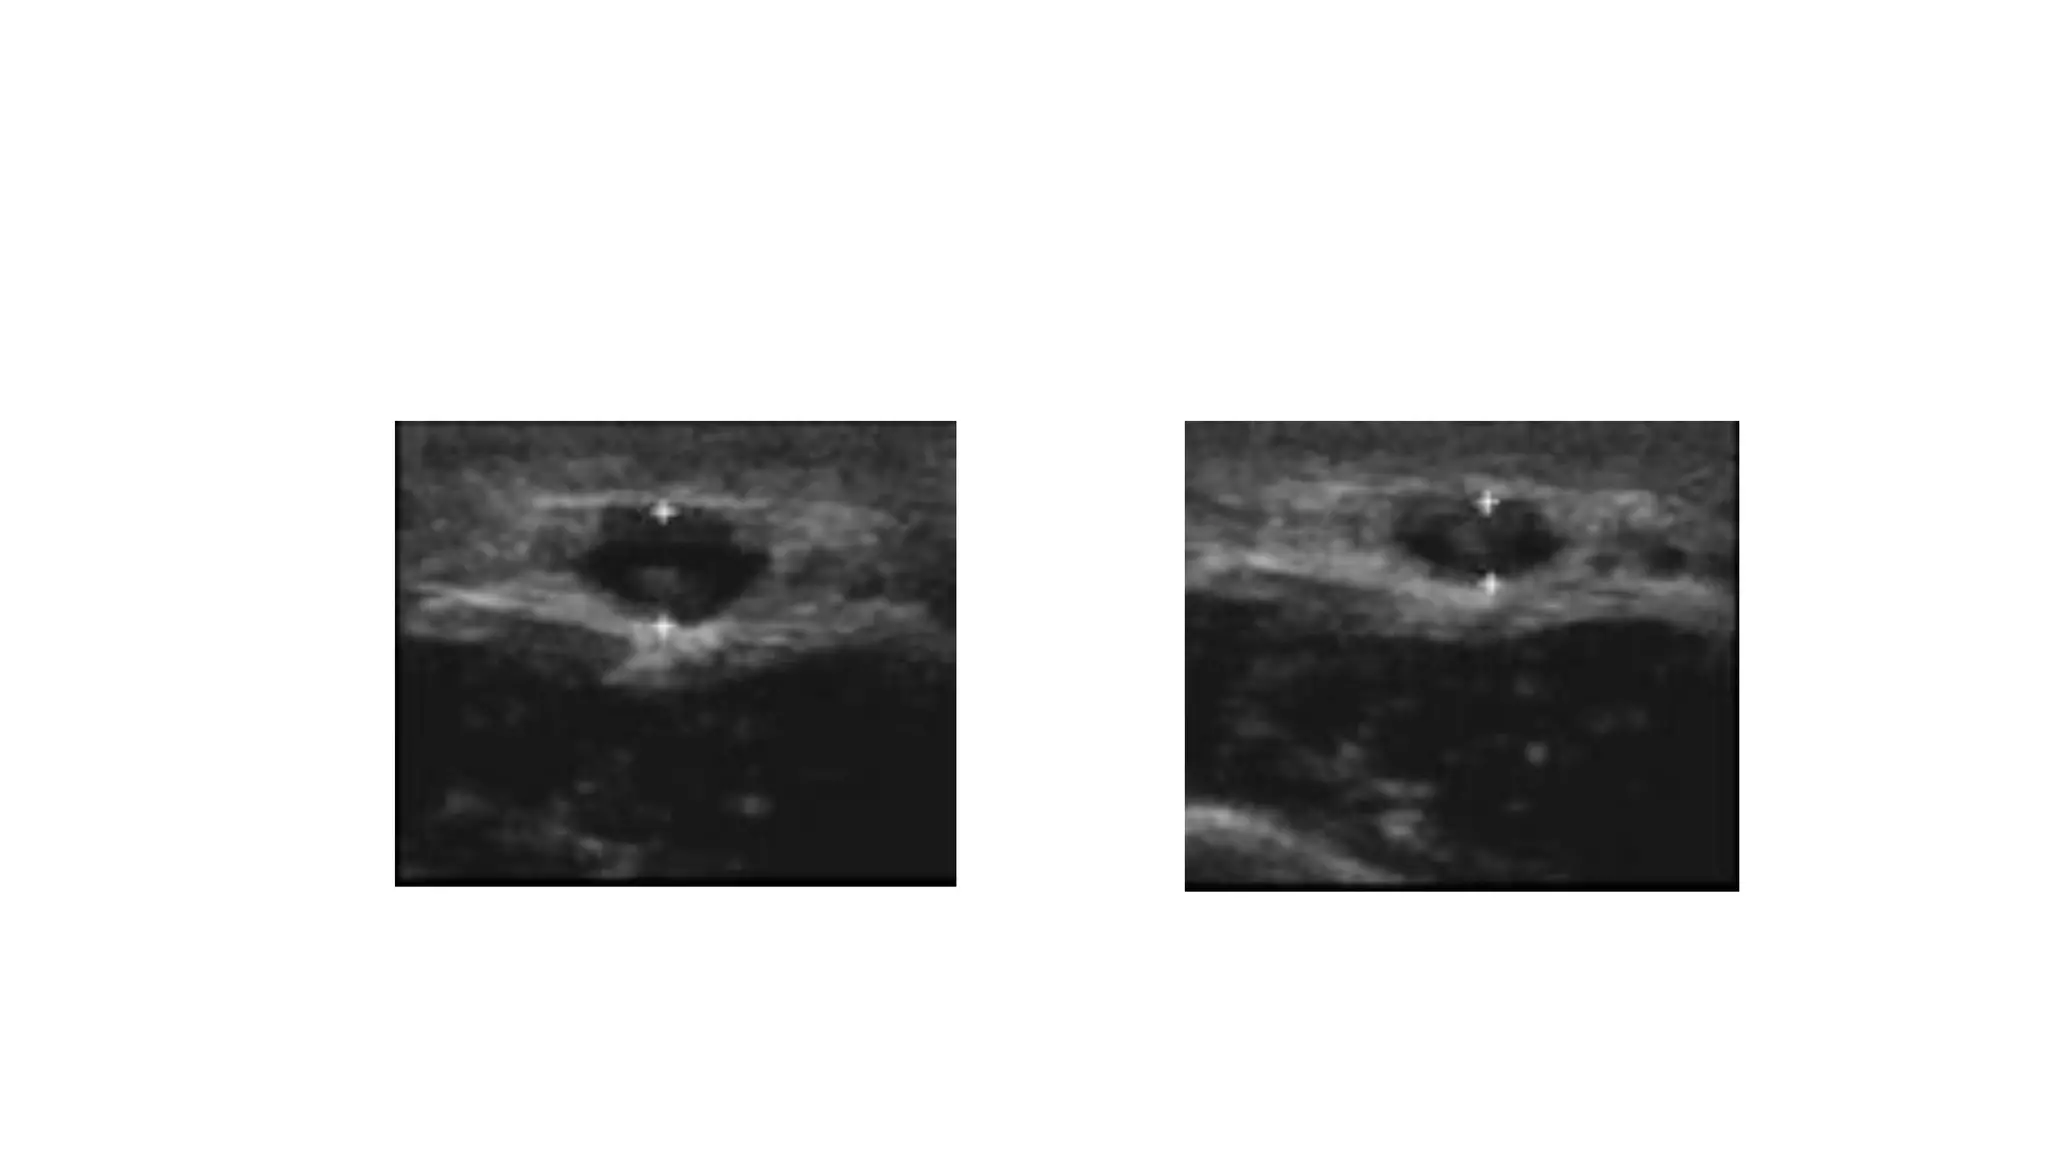

Ultrasound vascular mapping uses ultrasound to examine arteries and veins in the arms before dialysis access placement. It assesses vessel diameter, wall characteristics, blood flow, compressibility, and identifies the best vessels. The mapping examines arteries for internal diameter and wall appearance, uses Doppler to evaluate blood flow, and may check for calcification. It also assesses superficial arm veins for caliber, depth, wall appearance, distensibility, course, patency, and presence of collaterals to identify the best vessel options for dialysis access. A vein mapping worksheet is used to report the ultrasound findings.